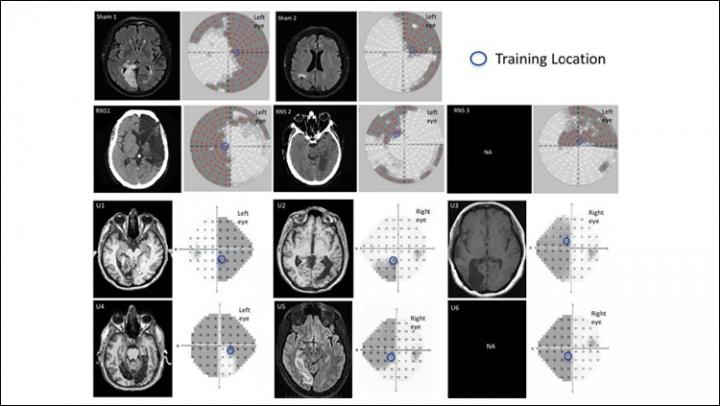

image: Neuroradiological images and visual perimetries of CB patients. All patients sustained damage of early visual areas or the optic radiations resulting in homonymous visual field defects as shown by the visual field perimetries, next to each brain image.

Herpich <em>et al</em>., <em>JNeurosci</em> (2019)